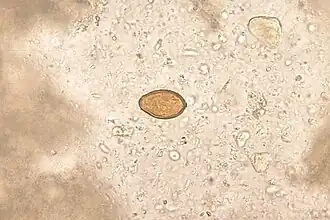

Heterophyes heterophyes é uma espécie de trematódeo da família Heterophyidae. É um parasita intestinal de humanos causando a heterofíase.[1]